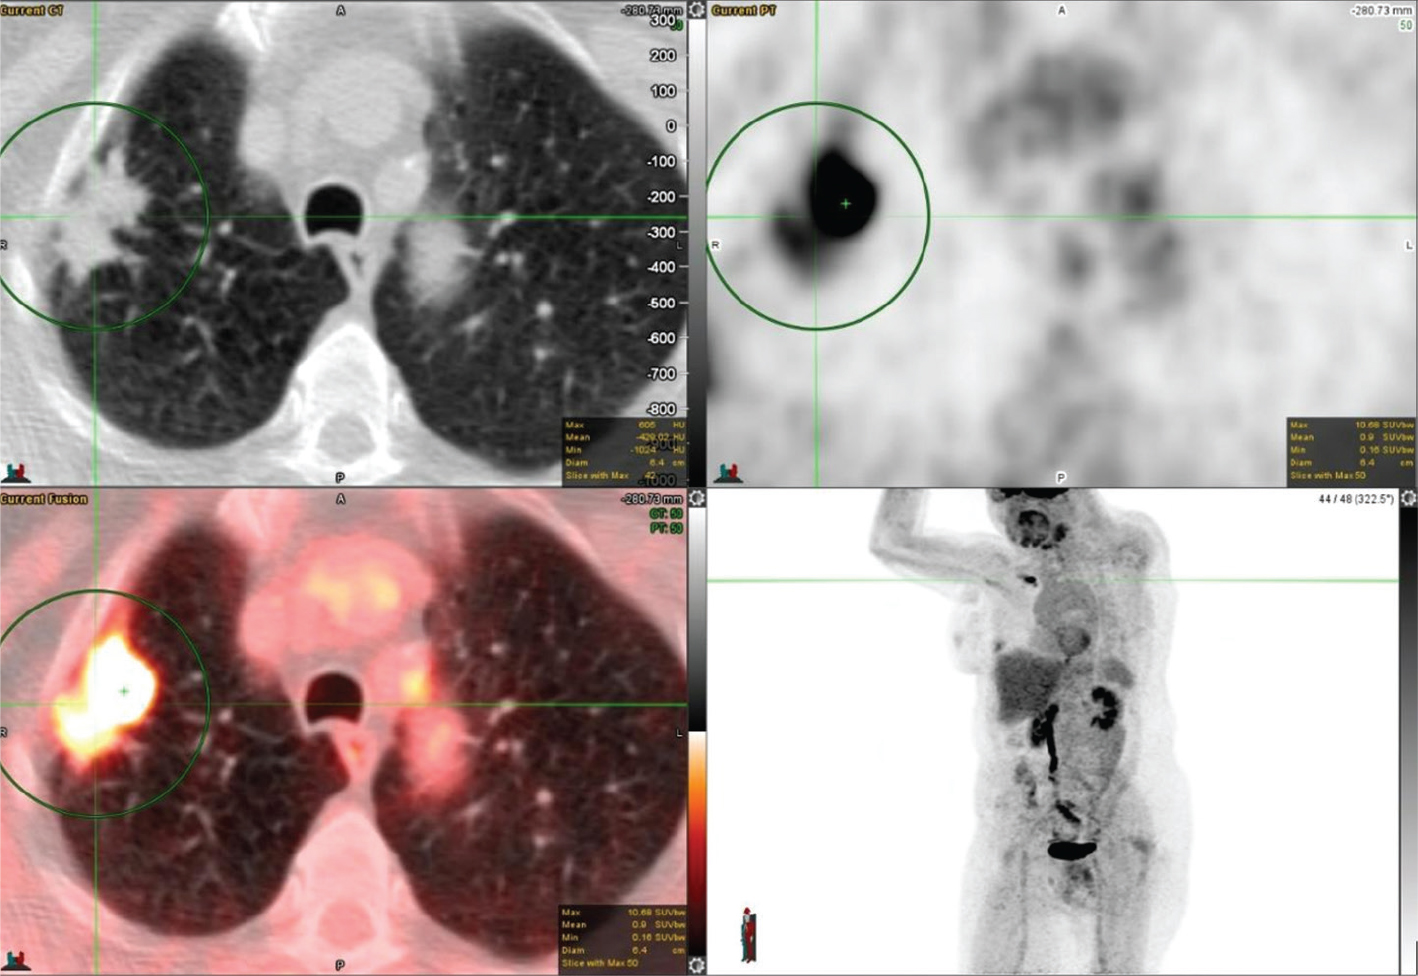

18F-FDG PET/CT has been widely studied for its use in the accurate characterization of SPNs because it localizes to the lesion proportionate to its metabolic activity. An example of an FDG avid SPN is shown in Figure 1. Solitary pulmonary nodules in PET/CT are analyzed qualitatively and quantitatively. Qualitatively, metabolic activity in the SPN is visually compared with the activity of the mediastinal blood pool; SNPs with metabolic activity greater than the mediastinal blood pool are likely malignant. For quantitative assessment, a standardized uptake value (SUV) can be used and SUV greater than 2.5 defines the SPNs as malignant with a relatively high degree of sensitivity and specificity (7). However, this 2.5 threshold is arbitrary as newer PET scanners generally provide higher uptake values than older machines. Additionally, the SUV is underestimated for small nodules due to the partial-volume effect, and for lower lung nodules near the diaphragm due to respiratory motion. Furthermore, in the past, when FDG PET imaging was a new modality, the 2.5 threshold was used, although it has been proven to be suboptimal subsequently, as low-grade malignancies can have low SUVs and active infectious/inflammatory etiologies can have high SUVs. However, SUV on 18F-FDG PET/CT correlates well with Ki-67 (a marker of cell proliferation) and the intensity of FDG uptake/SUV has a correlation with grade and aggressiveness of the lesion and consequently prognostic significance. Using these criteria, recent studies have shown a sensitivity of 92–96% and a specificity of 77–90% using 18F-FDG PET/CT for detecting malignancy (8). A multicenter study by Lowe et al. showed sensitivities of 100% and 80%, and specificities of 74% and 95%, for visual and SUV analyses of SPNs, respectively (9). A recent meta-analysis of studies using 18F-FDG PET/CT for the evaluation of SPNs showed a sensitivity of 96.8% and a specificity of 77.8% (7).

Fig 1

Figure 1. Right upper lung pulmonary nodule that was pathologically confirmed as invasive moderately differentiated adenocarcinoma. FDG PET/CT images include axial CT (top left panel), axial PET (top right panel), fused axial PET/CT (bottom left panel), and maximum intensity projection (MIP) PET image (bottom right panel). In the green circle, there is a right upper lobe pulmonary nodule on CT with intense FDG uptake on PET. There was additional mild to moderately FDG-avid lymph nodes (not on the included PET/CT images and faintly seen on the MIP image) that were suspicious for metastatic disease.